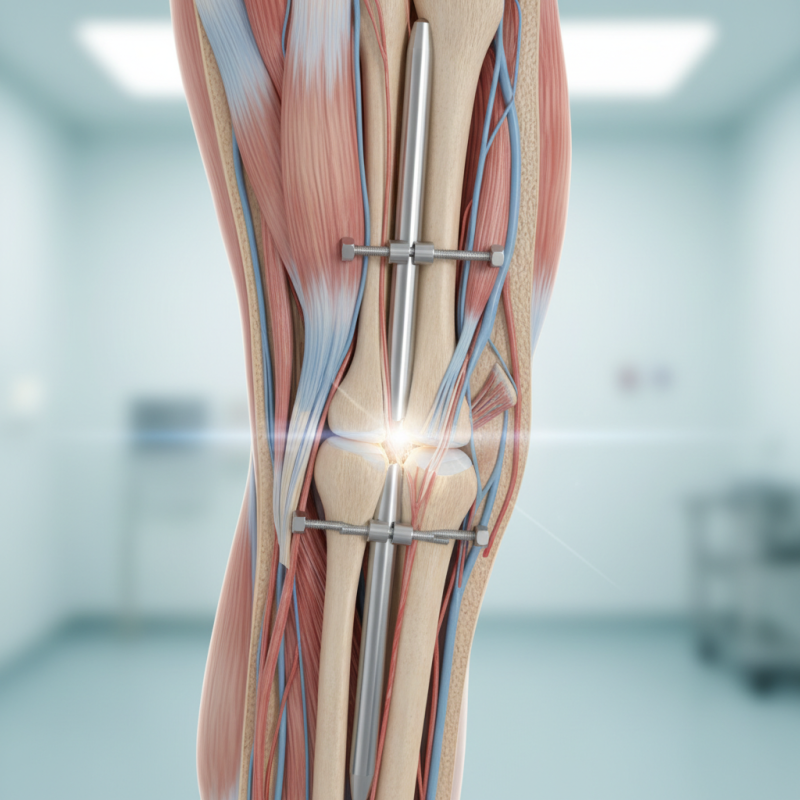

The tibial interlocking nail is a device used in orthopedic surgery. It treats fractures in the tibia, the main bone in the lower leg. This system stabilizes the bone internally. It is particularly useful for complex or long bone fractures. The nail is inserted through the skin and into the medullary cavity of the tibia. It allows for better alignment and healing.

This method features interlocking screws that secure the nail in place. These screws help resist rotational and axial forces. This feature gives the nail its "interlocking" name. Additionally, the procedure is minimally invasive compared to traditional surgeries. Recovery often benefits from reduced soft tissue damage. However, not all patients may achieve ideal outcomes. Some complications can arise, such as infection or nonunion.

The surgical procedure for inserting a tibial interlocking nail is a common approach for treating fractures in the tibia. Surgeons typically perform this operation under general or regional anesthesia. The aim is to stabilize the fracture, allowing for proper healing. A specific nail designed for this purpose is inserted through a small incision. The procedure often includes a guide wire placement to ensure accuracy during insertion.

After the nail is positioned within the medullary canal, locking screws secure it to the bone. This enhances stability, particularly in complex fractures. Data shows that using tibial interlocking nails can lead to a 90% success rate in fracture healing within a specified timeframe. However, complications can arise, such as infection or non-union of the fracture. It's crucial for patients to understand these risks.

Mechanism of Action: How the Nail Stabilizes Bone Fractures

Tibial interlocking nails are essential in treating long bone fractures. They provide immediate stability through a combination of intramedullary insertion and locking mechanisms. This device effectively reduces malalignment and enhances healing. According to a study published in the Journal of Orthopaedic Trauma, over 80% of patients showed significant improvement in bone regrowth within six months of using these nails.

The mechanism of action is straightforward yet profound. Once the nail is inserted into the tibia, it aligns the bone ends. The locking screws then provide additional fixation. This dual support helps maintain alignment during healing. A 2019 analysis indicated that the failure rate of tibial fractures treated with interlocking nails was lower than 10%. However, complications like infection or improper placement can occur, highlighting room for improvement in technique and preoperative planning.